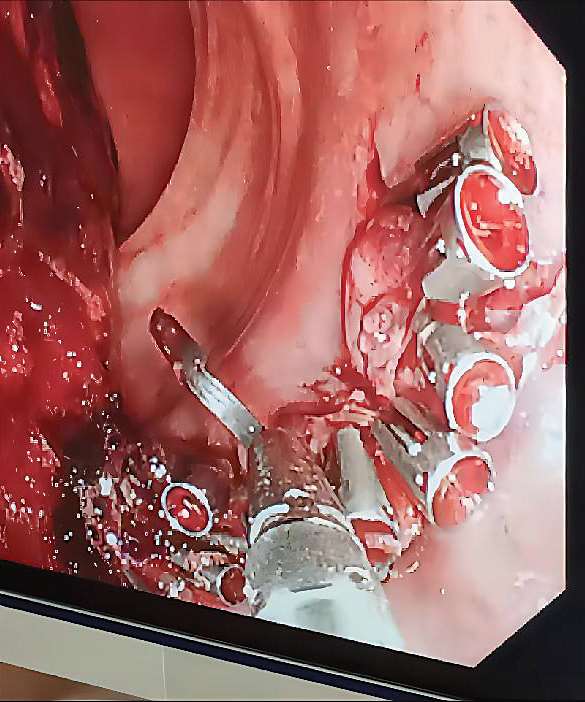

梁林江认为,痔病是良性疾病,对于良性疾病的治疗,最基本的原则就是不能给患者造成不必要的伤害,增加不必要的痛苦。无症状的痔对人体健康没有明显影响,所以我们的治疗也就应该针对有症状的痔体,锁定治疗边界。医生不要为了炫技而过度手术,或者扩大手术范围,将原本简单的治疗复杂化,使患者承受附加的痛苦。比如,部分经历过PPH治疗的患者会产生肛门坠胀疼痛感,严重者可持续数年,影响正常生活,甚至产生焦虑、抑郁的情绪。不可否认,因为我们对自己的身体结构、功能及其相互间影响的结果还没有透彻的了解,手术总有并发症、后遗症。正因为如此,医生在选择治疗方式时更应该慎重,避免掺杂其他社会因素的影响。图片中的患者10 年前接受了PPH治疗,出现肛门持续疼痛,肛门指诊可以触摸到后中齿线黏膜下的残钉,有触痛,由此长期炎症刺激导致多发肛乳头肥大,手术将残钉取出后,疼痛感即解除(图 2—25 ~图 2—28)。

图 2—25 黑色箭头所指为残钉在CT中的显影

图 2—26 慢性炎症造成多发性肛乳头肥大

图 2—27 手术取下的残钉

图 2—28 手术切除多发性肛乳头肥大